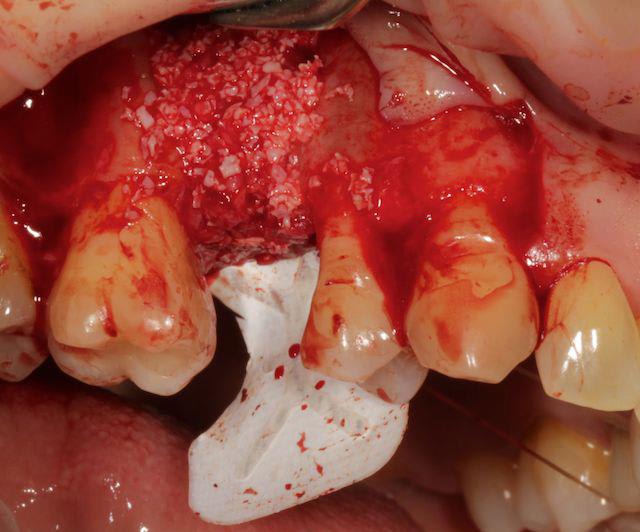

tiens pour faire avancer le débat un cas de ROG verticale et horizontale, avec membrane PTFE armé titane.

à la mandibule, non je n'ai pas fait de photos avec la membrane, trop compliqué dans ce cas là, surtout pour ce qu'en fait, j'ai mis un mélange bio-oss autogéne à 50/50 le tout recouvert par un bio-gide securisée par des pin's.